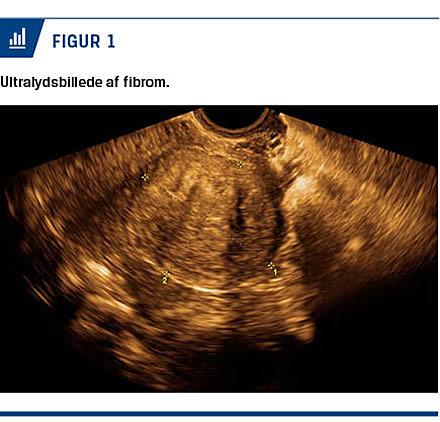

Mistanken om fibromer fås ved en gynækologisk undersøgelse. Ved en vaginal ultralydskanning vil man oftest kunne bekræfte diagnosen på grund af fibromernes karakteristiske ultrasoniske udseende (Figur 1). Supplerende MR-skanning er nyttig for mere eksakt bestemmelse af antal og lokalisation ved multiple eller store fibromer [9].